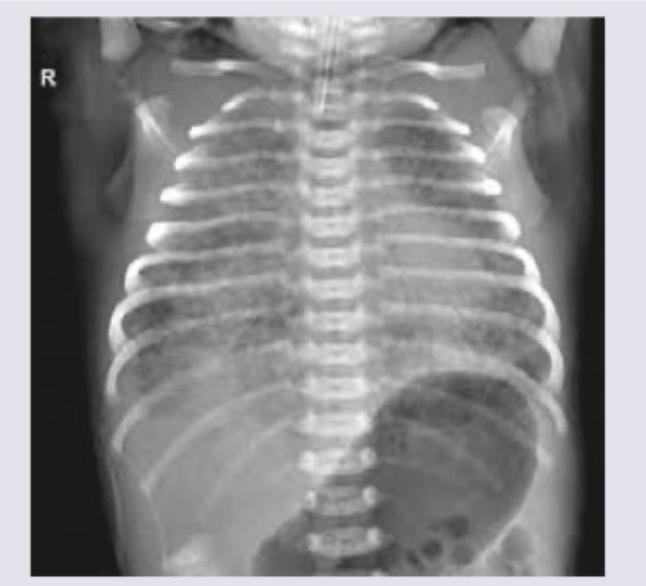

Child has not passed stool by 2nd day of life. X-Ray study done shows:

Explanation: ***Duodenal atresia*** - The abdominal X-ray images display the classic **"double bubble sign"**, which is highly characteristic of duodenal atresia. This sign consists of two distinct air-filled loops, one representing the distended stomach and the other the dilated proximal duodenum, with no distal gas. - The clinical presentation of a neonate not passing stool by the second day of life, combined with the characteristic radiological findings, points directly to an **upper gastrointestinal obstruction** like duodenal atresia. *Cystic fibrosis* - While cystic fibrosis can cause **meconium ileus** leading to intestinal obstruction in newborns, it typically presents with diffuse intestinal distension rather than the localized "double bubble" pattern. - Meconium ileus on X-ray would show numerous dilated loops of small bowel with a **"ground-glass" appearance** due to trapped meconium, not the distinct two bubbles seen here. *CHPS* - **Congenital hypertrophic pyloric stenosis (CHPS)** typically manifests later, between 3-6 weeks of age, with projectile non-bilious vomiting, not as early as the second day of life with findings of intestinal obstruction on X-ray. - The X-ray findings in CHPS would show a **distended stomach but without the second bubble** representing a dilated duodenum often seen in duodenal atresia. *Anorectal malformation* - **Anorectal malformations** are lower gastrointestinal obstructions, meaning a significant portion of the bowel would be distended with gas, and the X-ray would not show the isolated "double bubble" sign. - Diagnosis is often made by physical examination demonstrating an **imperforate anus** or abnormal anal opening, in conjunction with plain abdominal radiographs that would show distal intestinal obstruction.